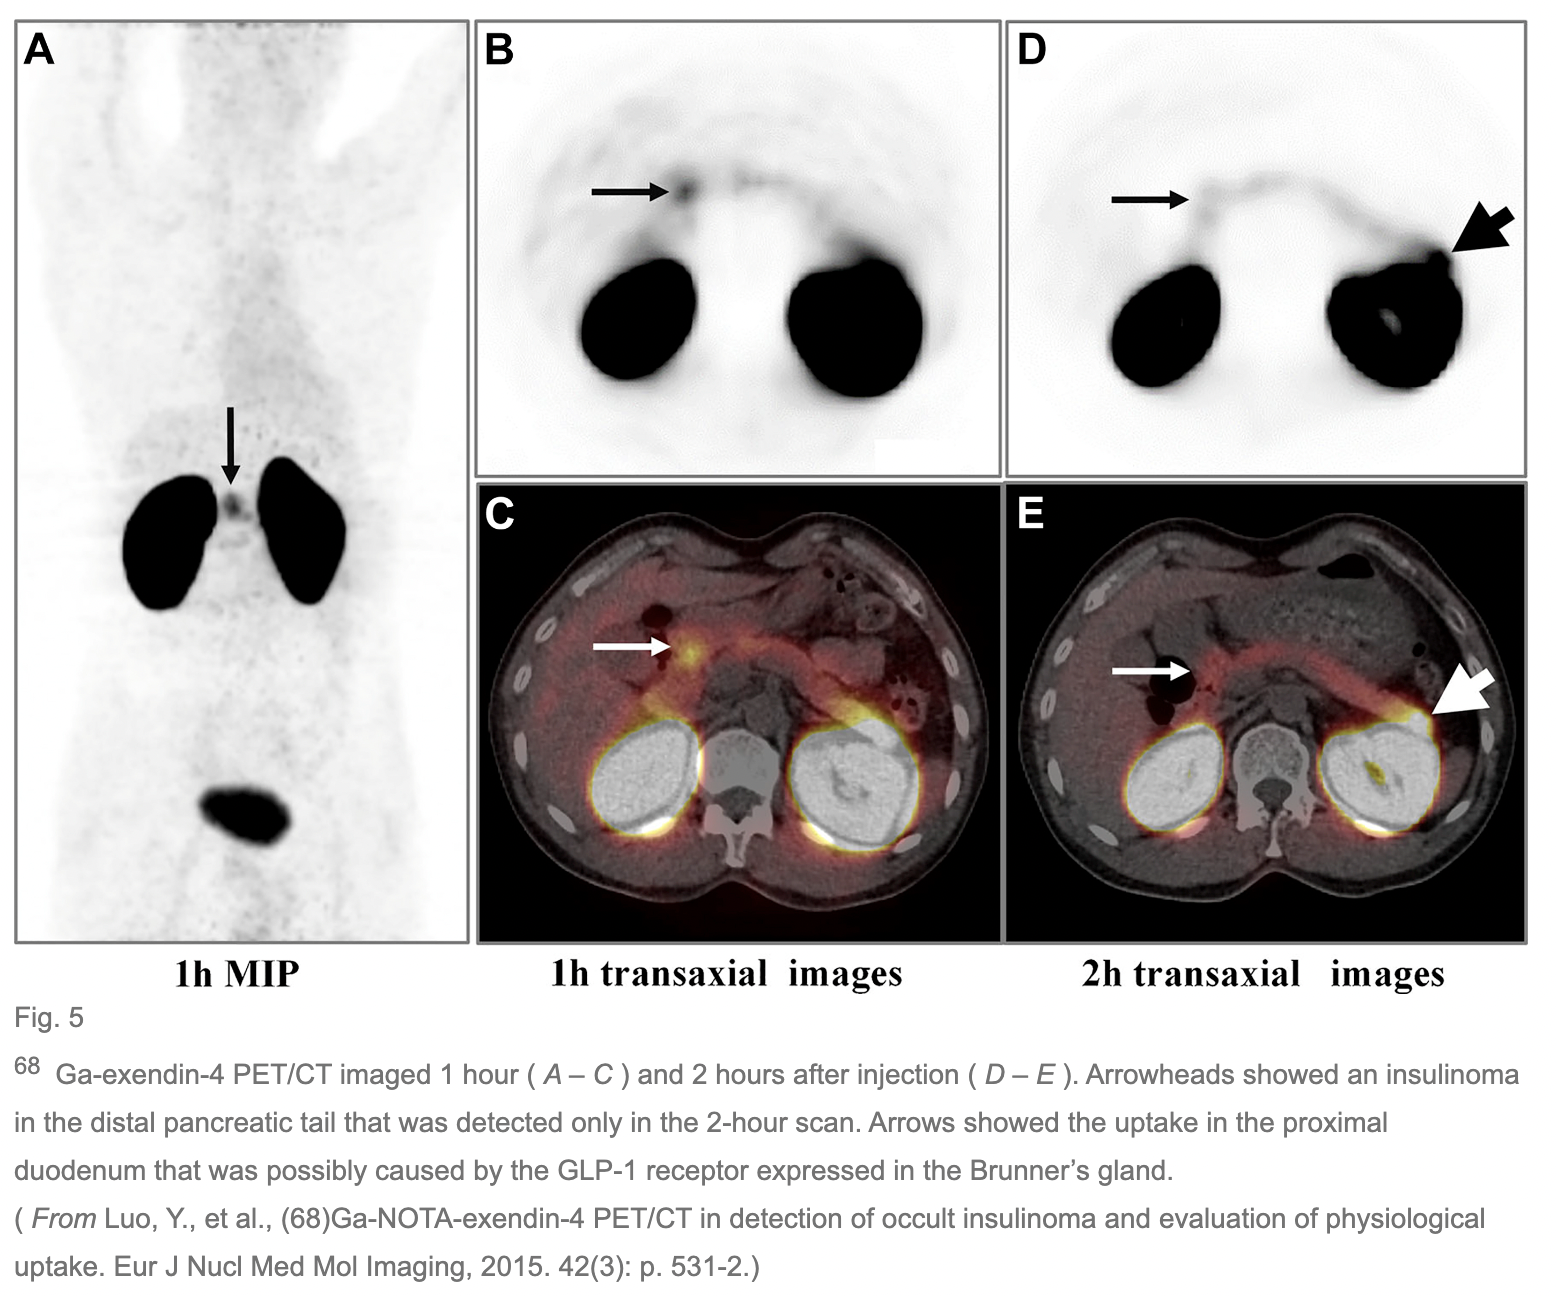

• High physiologic expression of GLP-1 receptor is noted in the brunners gland in proximal duodenum, therefore there is physiological uptake in the duodenum, which can lead to false interpretation.

• Renal excretion of exendin -4 interfere with detection of insulinoma in distal pancreas tail located near to the left kidney. Megalin mediated reabsorption in the proximal tubules after glomerular filtration is responsible for renal retension of tracer.